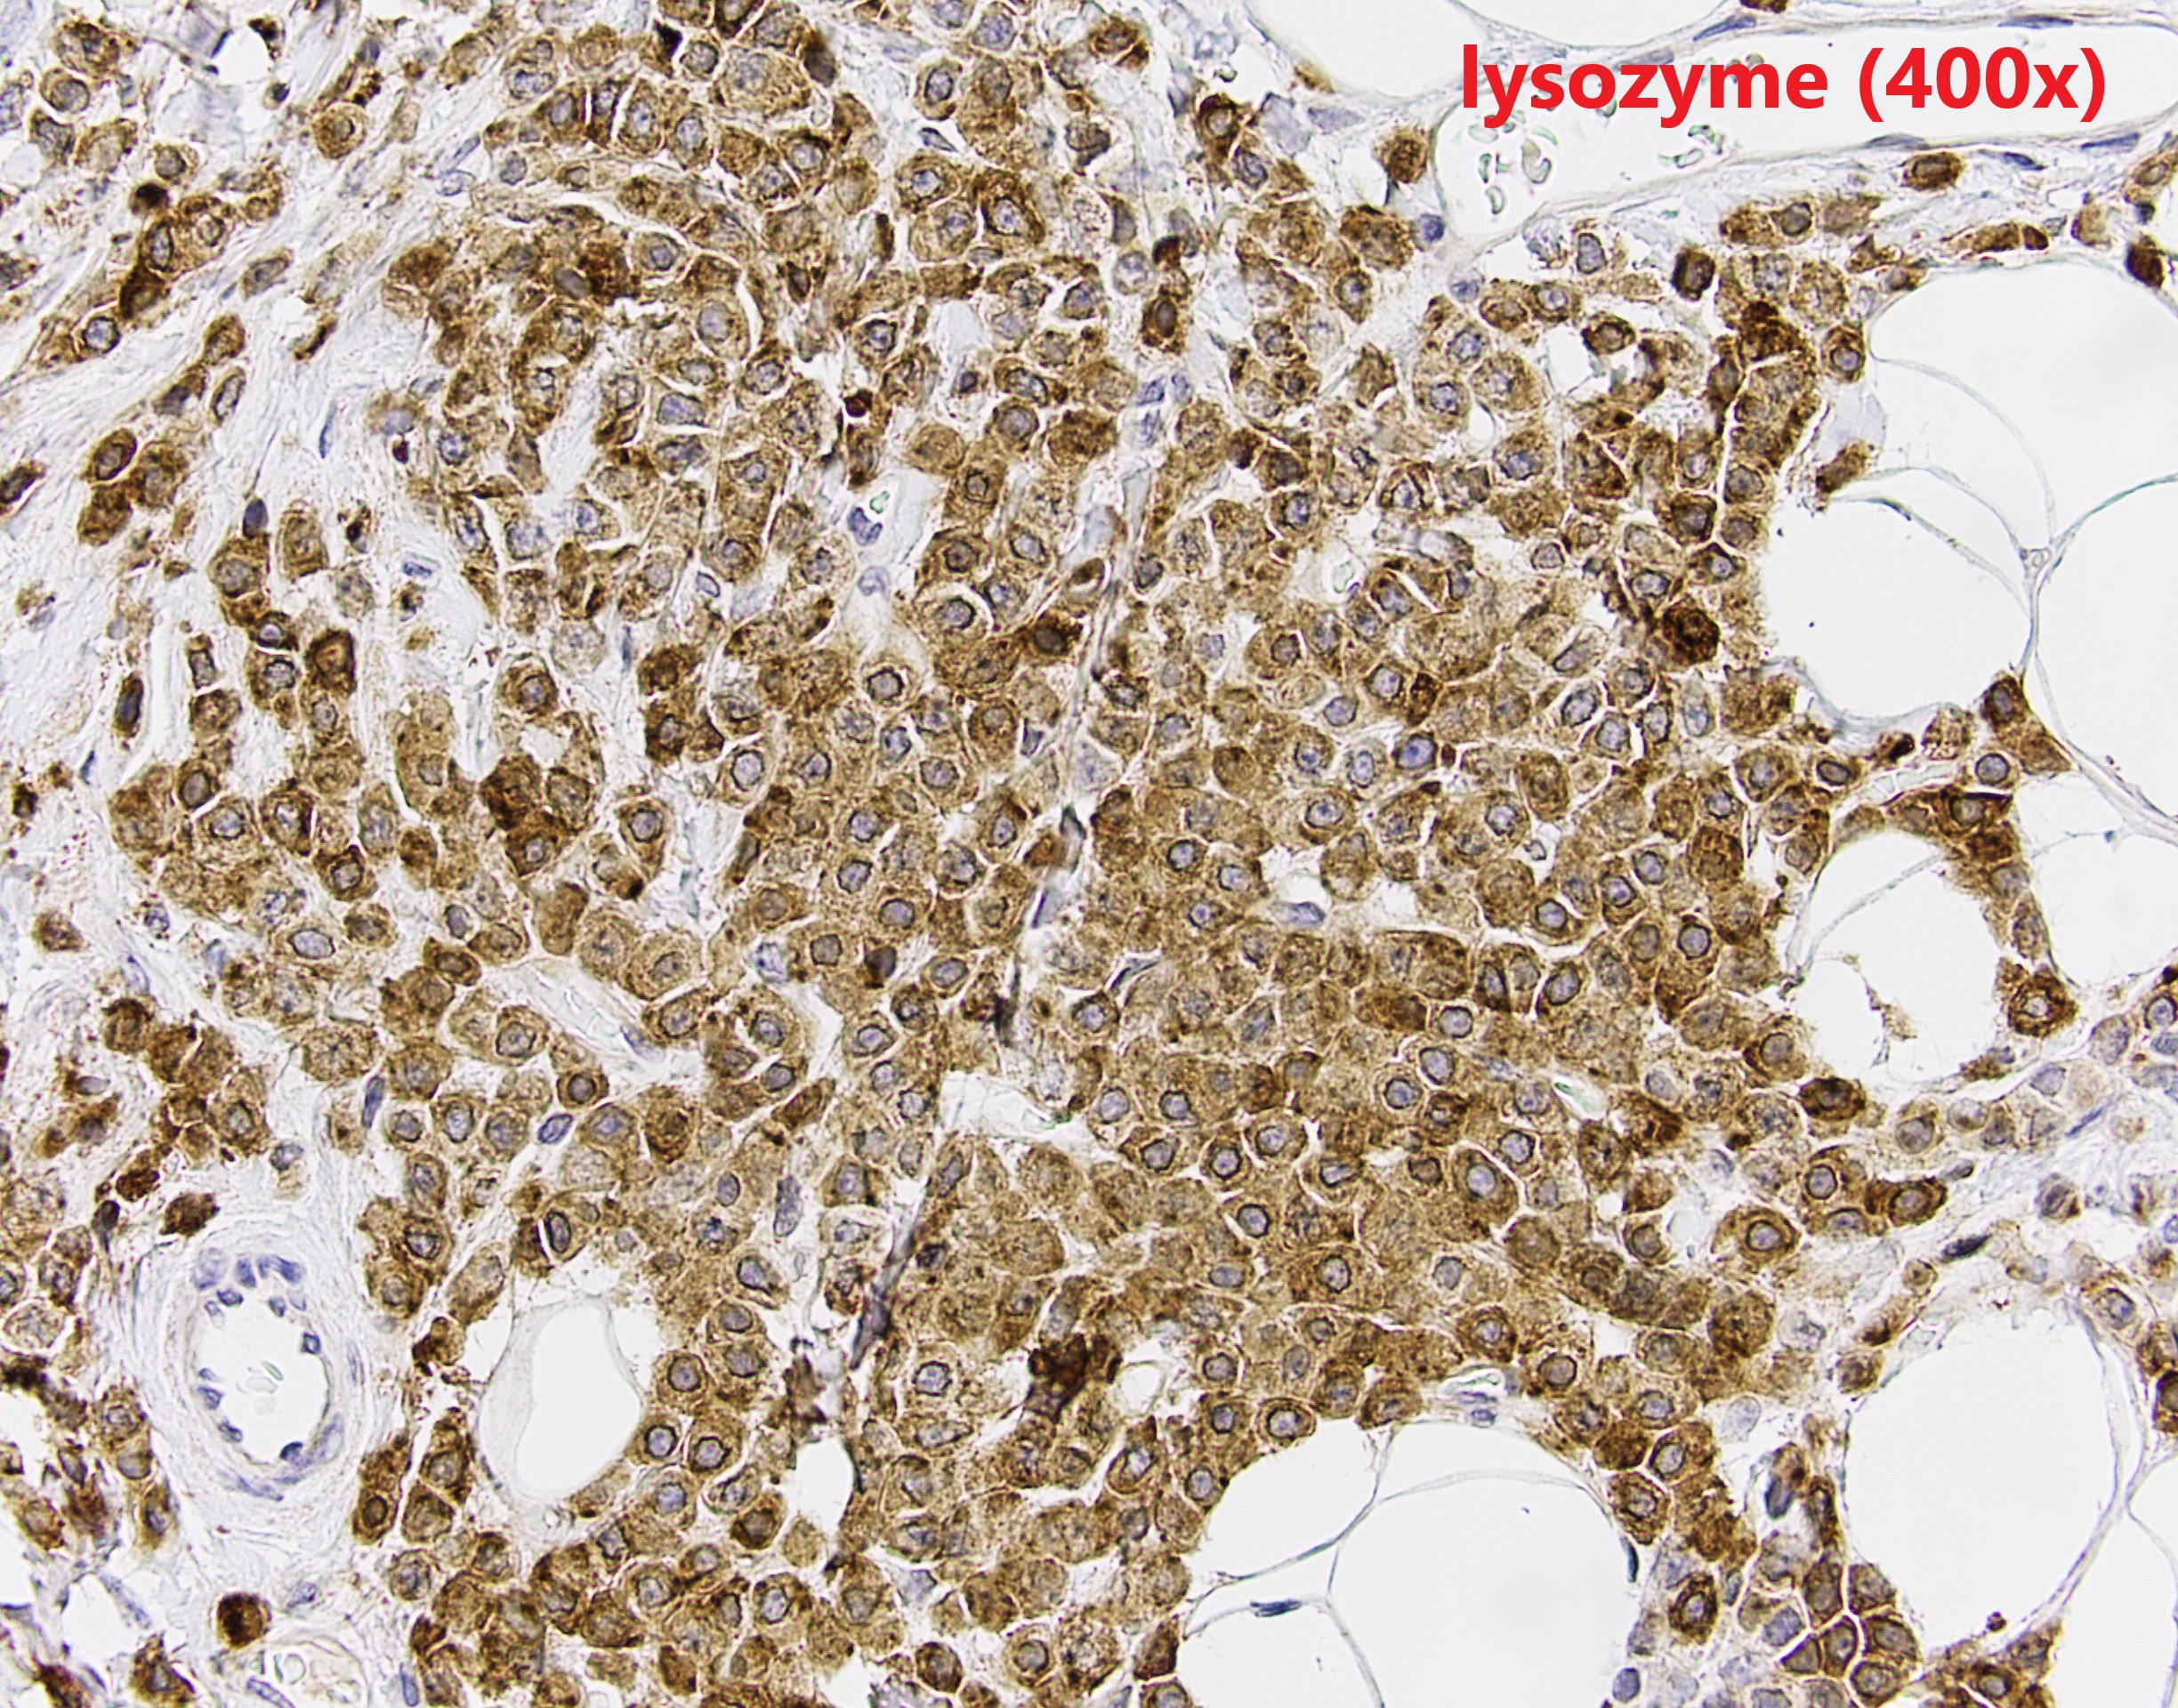

The patient is a middle-aged female with an irregular enhancing mass in the right breast. After resection, IHC revealed GATA3 and CK7 positivity and p63 negativity. Further studies of lysozyme and a1-antichymotrypsin are shown.

Breast acinic cell carcinoma (ACC) is a rare entity and usually affects women aged 20-80 years. Architectural patterns of ACC are variable, ranging from microglandular proliferation to solid. Diagnosis of ACC is mainly based on cytological features. The tumor cells show abundant eosinophilic to clear cytoplasm with coarse granules. The nuclei are usually centrally located with prominent nucleoli. Cytological atypia and mitosis can be seen. The tumor cells are usually triple negative, and positive for S100, EMA, lysozyme and α1-antichymotrypsin. The differential diagnosis is broad depends on cytomorphology. The prognosis of ACC is still unclear because the limited number of cases reported. Most of the reported patient had chemoradiation and surgery.